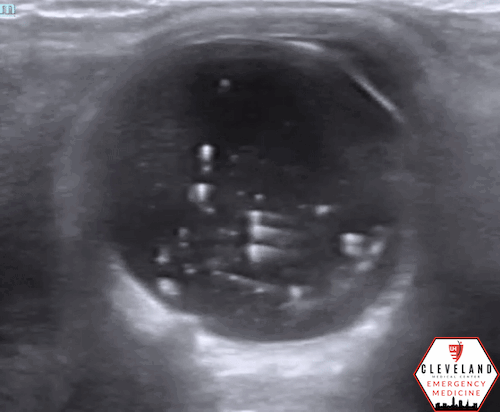

POCUS Findings: There was no evidence of retinal detachment visualized but there are multiple distinct mobile hyperechoic structures within the vitreous body. Findings are somewhat similar to vitreous hemorrhage, but the particles are more discrete and hyperechoic compared to typical findings seen with vitreous hemorrhage/detachment. This is suggestive of asteroid hyalosis.

Asteroid hyalosis, named for resembling “stars in the night sky,” is a benign vitreous condition resulting in calcium phospholipid deposits, varying in size, within the posterior chamber [1]. It’s been shown to strongly correlate with increasing age, male sex, and lack of vitreous detachment, but the etiology is not well known. Often asymptomatic, it’s often an incidental finding and typically doesn’t require any intervention [2].

AH can be easily misinterpreted as vitreous hemorrhage on POCUS as both pathologies produce numerous echogenic opacities and have the classic “washing machine” appearance with extraocular movement. AH tends to have more brighter, more discrete, scintillating particles throughout the vitreous, whereas VH is generally more heterogeneous and layers in the posterior aspect of the vitreous [3-5].